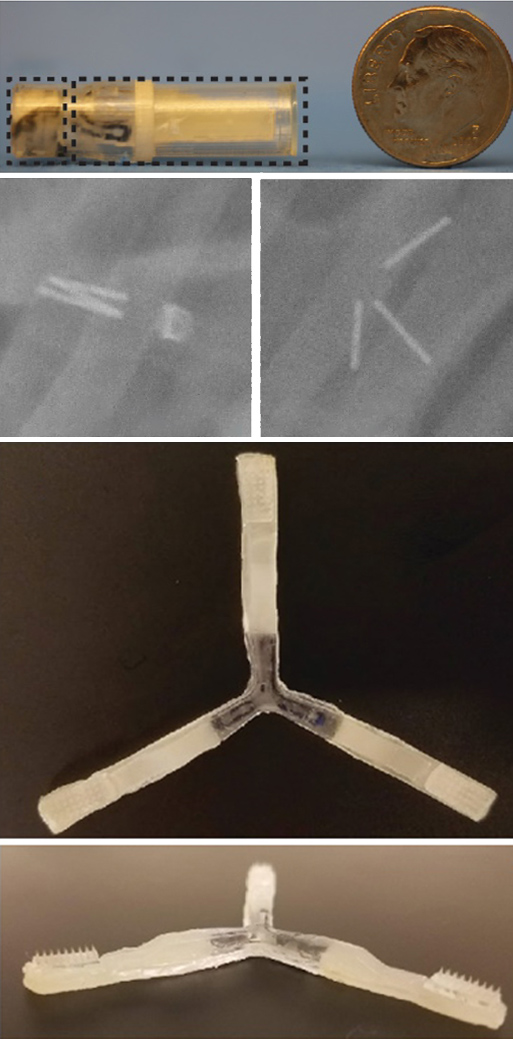

The team developed an ingestible capsule they named the “luminal unfolding microneedle injector” or LUMI. The device is roughly the size of a pen cap, measuring 9 mm (.35 inches) in diameter and 30 mm (1.2 inches) in length.

The capsule protects the LUMI during the acidic journey through the stomach and ejects the LUMI when it reaches the small intestine. Three spring-loaded arms extend, pushing a cluster of 1-mm long microneedles into the tissue wall of the small intestine. These microneedles dissolve, releasing the medication. The drug is then carried to the bloodstream.

The researchers developed their design based on tests using pigs and lengths of small intestine taken from humans. They worked to ensure that the microneedles penetrated the surface of the tissue without tearing through. Tests helped determine the ideal length of the device’s microneedles and the force with which the arms were deployed. The researchers note that the small intestine has few pain receptors. This ensures that the injections are not painful.